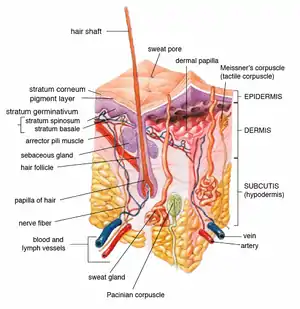

Insertion of sebaceous glands into hair shaft

Insertion of sebaceous glands into hair shaft Cross-section of all skin layers

Cross-section of all skin layers